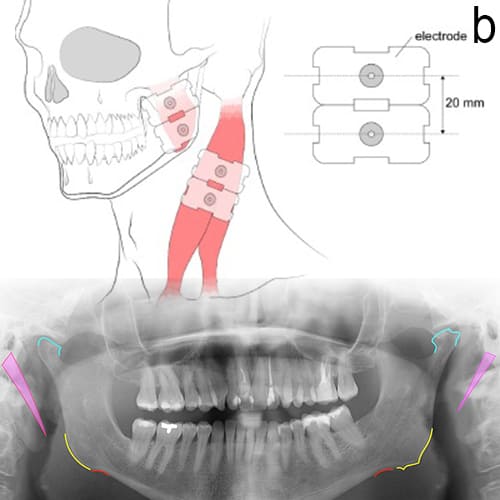

• Understanding Pain Patterns: Pain from trigger points can refer to different parts of the body, leading to confusion in diagnosis. For example, tension in the masseter muscle may cause pain that feels like a toothache or headache. Recognizing these referral patterns helps dentists accurately diagnose orofacial pain and tailor effective treatment strategies, such as trigger point injections or physical therapy.

• Assessing the Pain: The dentist conducts a thorough examination of the jaw, mouth and neck, checking for trigger points in the muscles that might refer pain to other areas. Imaging tests like X-rays, MRI, electromyography or CT scans may also be used to rule out dental problems or structural issues contributing to the pain.